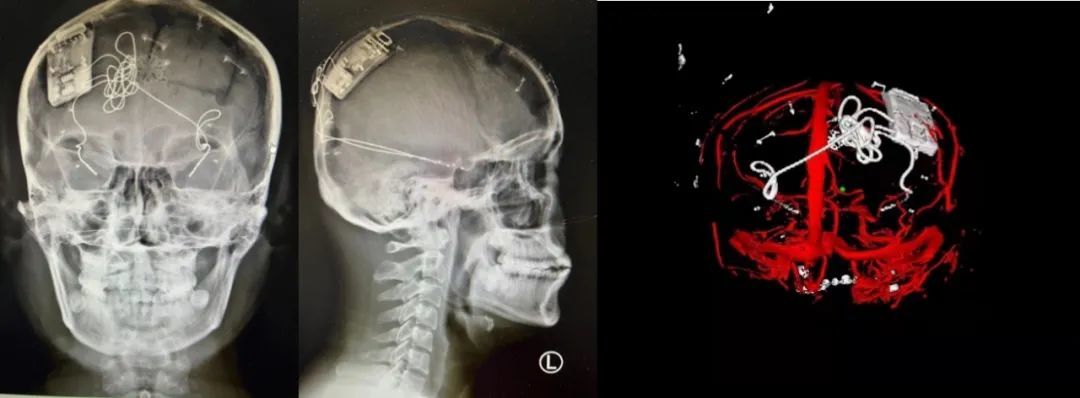

本次手術(shù)過程順利,術(shù)中刺激器各項(xiàng)指標(biāo)均工作正常,術(shù)后重建顯示電極位置精準(zhǔn),腦電信號(hào)清晰?;颊邽槟行?,入院后診斷為雙側(cè)顳葉癲癇,此類癲癇為開顱手術(shù)的相對(duì)禁忌癥,在藥物無法控制的情況下,傳統(tǒng)治療效果欠佳 。

術(shù)前經(jīng)過宣武醫(yī)院癲癇多學(xué)科專家團(tuán)隊(duì)詳細(xì)的臨床評(píng)估,包括視頻腦電監(jiān)測(cè)、頭顱磁共振及三維 CT 掃描、腦核醫(yī)學(xué)檢查等,全面評(píng)估了患者病情及致癇灶定位情況。

由于患者臨床診斷為雙側(cè)顳葉癲癇伴海馬硬化,無法通過致癇灶切除等傳統(tǒng)外科手術(shù)方式獲益,決定進(jìn)行閉環(huán)反應(yīng)性神經(jīng)刺激系統(tǒng)植入手術(shù)治療。并根據(jù)閉環(huán)神經(jīng)刺激技術(shù)特點(diǎn),為患者“量身定制”植入方案,尤其是電極植入位點(diǎn)和脈沖發(fā)生器固定部位等,為手術(shù)的順利實(shí)施奠定了良好基礎(chǔ)。

團(tuán)隊(duì)根據(jù)術(shù)前計(jì)劃,在手術(shù)機(jī)器人輔助下完成雙海馬長(zhǎng)軸電極及 IPG 植入,術(shù)后重建顯示電極位置精準(zhǔn),腦電信號(hào)清晰。術(shù)后第二天,患者即下床活動(dòng),身體狀況恢復(fù)良好。